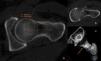

El pinzamiento femoroacetabular es una entidad patológica que se presenta en las consultas del aparato locomotor y que cursa con dolor e impotencia funcional de la cadera en el adulto joven. Se produce por un conflicto de espacio entre el componente femoral y el anillo acetabular en determinadas posiciones de la cadera. El origen puede estar en un defecto en la unión cabeza-cuello femoral, en un exceso de cobertura de la parte anterolateral del acetábulo o en ambas. Se desencadena un atrapamiento entre la unión cabeza-cuello y el reborde acetabular, que conducirá a una lesión inicial en la unión condrolabral y cuya evolución, si no se corrige, produce una degeneración precoz de la articulación.

Femoroacetabular impingement is a new pathological entity that is becoming more frecuently recognized in consults related to locomotor system. It appears when, due to a malformation in the femoral neck-head junction, a relative excess of bone in the anterolateral part of the acetabullum or both conditions together, a impingement is developed during the arc of movement of the joint, resulting in an initial chondrolabral lesion, being source of symptoms and functional impairment in the young patient. In case of no correction it will probably leads to secondary osteoarthritis when the cartilage lesion progress.